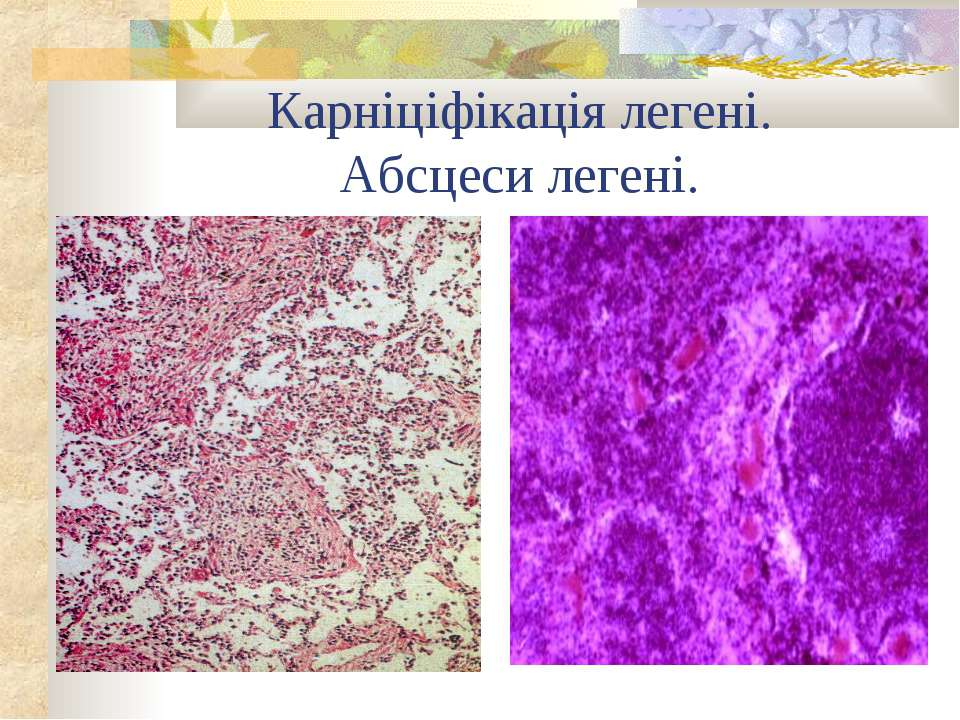

Карнификация Легкого: Микропрепараты и Диагностика

Раздел: Калейдоскоп образов